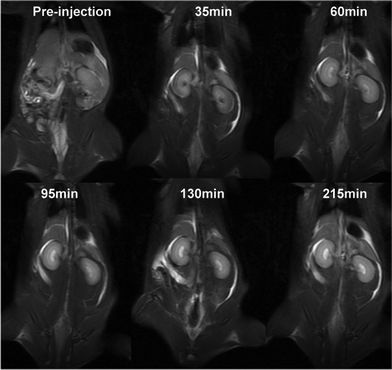

The effects of the contrast agents were tested in rats (Fig. 3). The injection of the agents resulted in clearer images of kidneys and blood vessels. Furthermore, the images show that three hours after injection, the agents were mainly in the kidney, suggesting a renal excretion of the contrast agent.

In vivo MR coronal images of a rat before and after intravenous injection of (Gd-DO3A)2-BMQX at a dose of 0.1 mmol Gd kg−1 weight. Animal care and handing procedures were in agreement with the guidelines of the Regional Ethics Committee for Animal Experiments.

Fig. 3 In vivo MR coronal images of a rat before and after intravenous injection of (Gd-DO3A)2-BMQX at a dose of 0.1 mmol Gd kg−1 weight. Animal care and handing procedures were in agreement with the guidelines of the Regional Ethics Committee for Animal Experiments.